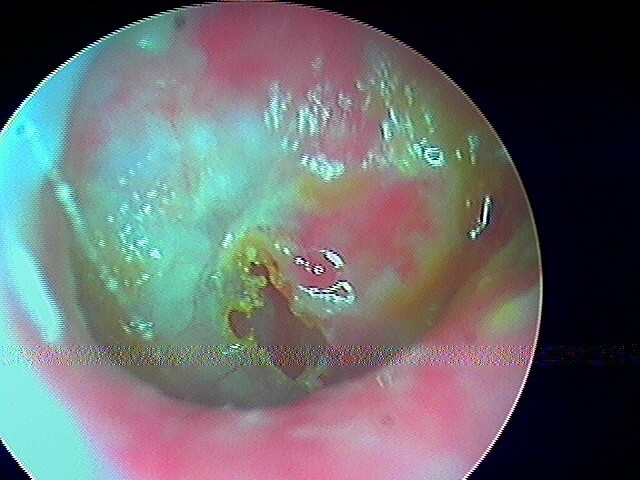

2/6 cholestéatome du CAE

Rare le cholestéatome du CAE, le tympan étant normal. Le diagnostic otoscopique est posé par la présence de squames et d'érosion osseuse. Ce sont des patients qui font des otites externes très rapprochées.

Post-opératoire à 1 an (le cadre osseux s'est reconstitué seul, j'avais juste fraisé):

Post-opératoire à 2 ans:

Post-opératoire à 3 ans: